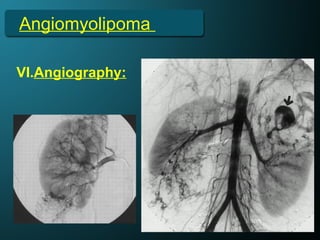

V. Angiography:

• 95% of AMLs are hypervascular.

• Enlarged interlobar and interlobular arteries.

• Intratumoral arteries are tortuous, irregular, and

aneurysmal.

• Venous pooling exists, with a sunburst, whorled, and

onion-peel appearance.

• No arteriovenous (AV) shunting is present.

Angiomyolipoma

VI.Angiography:

• The presence of multisacculated pseudoaneurysms, the

absence of AV shunting, a sunburst appearance of the

capillary nephrogram, and an onion-skin appearance of

the peripheral vessels in the venous phase suggest AML.